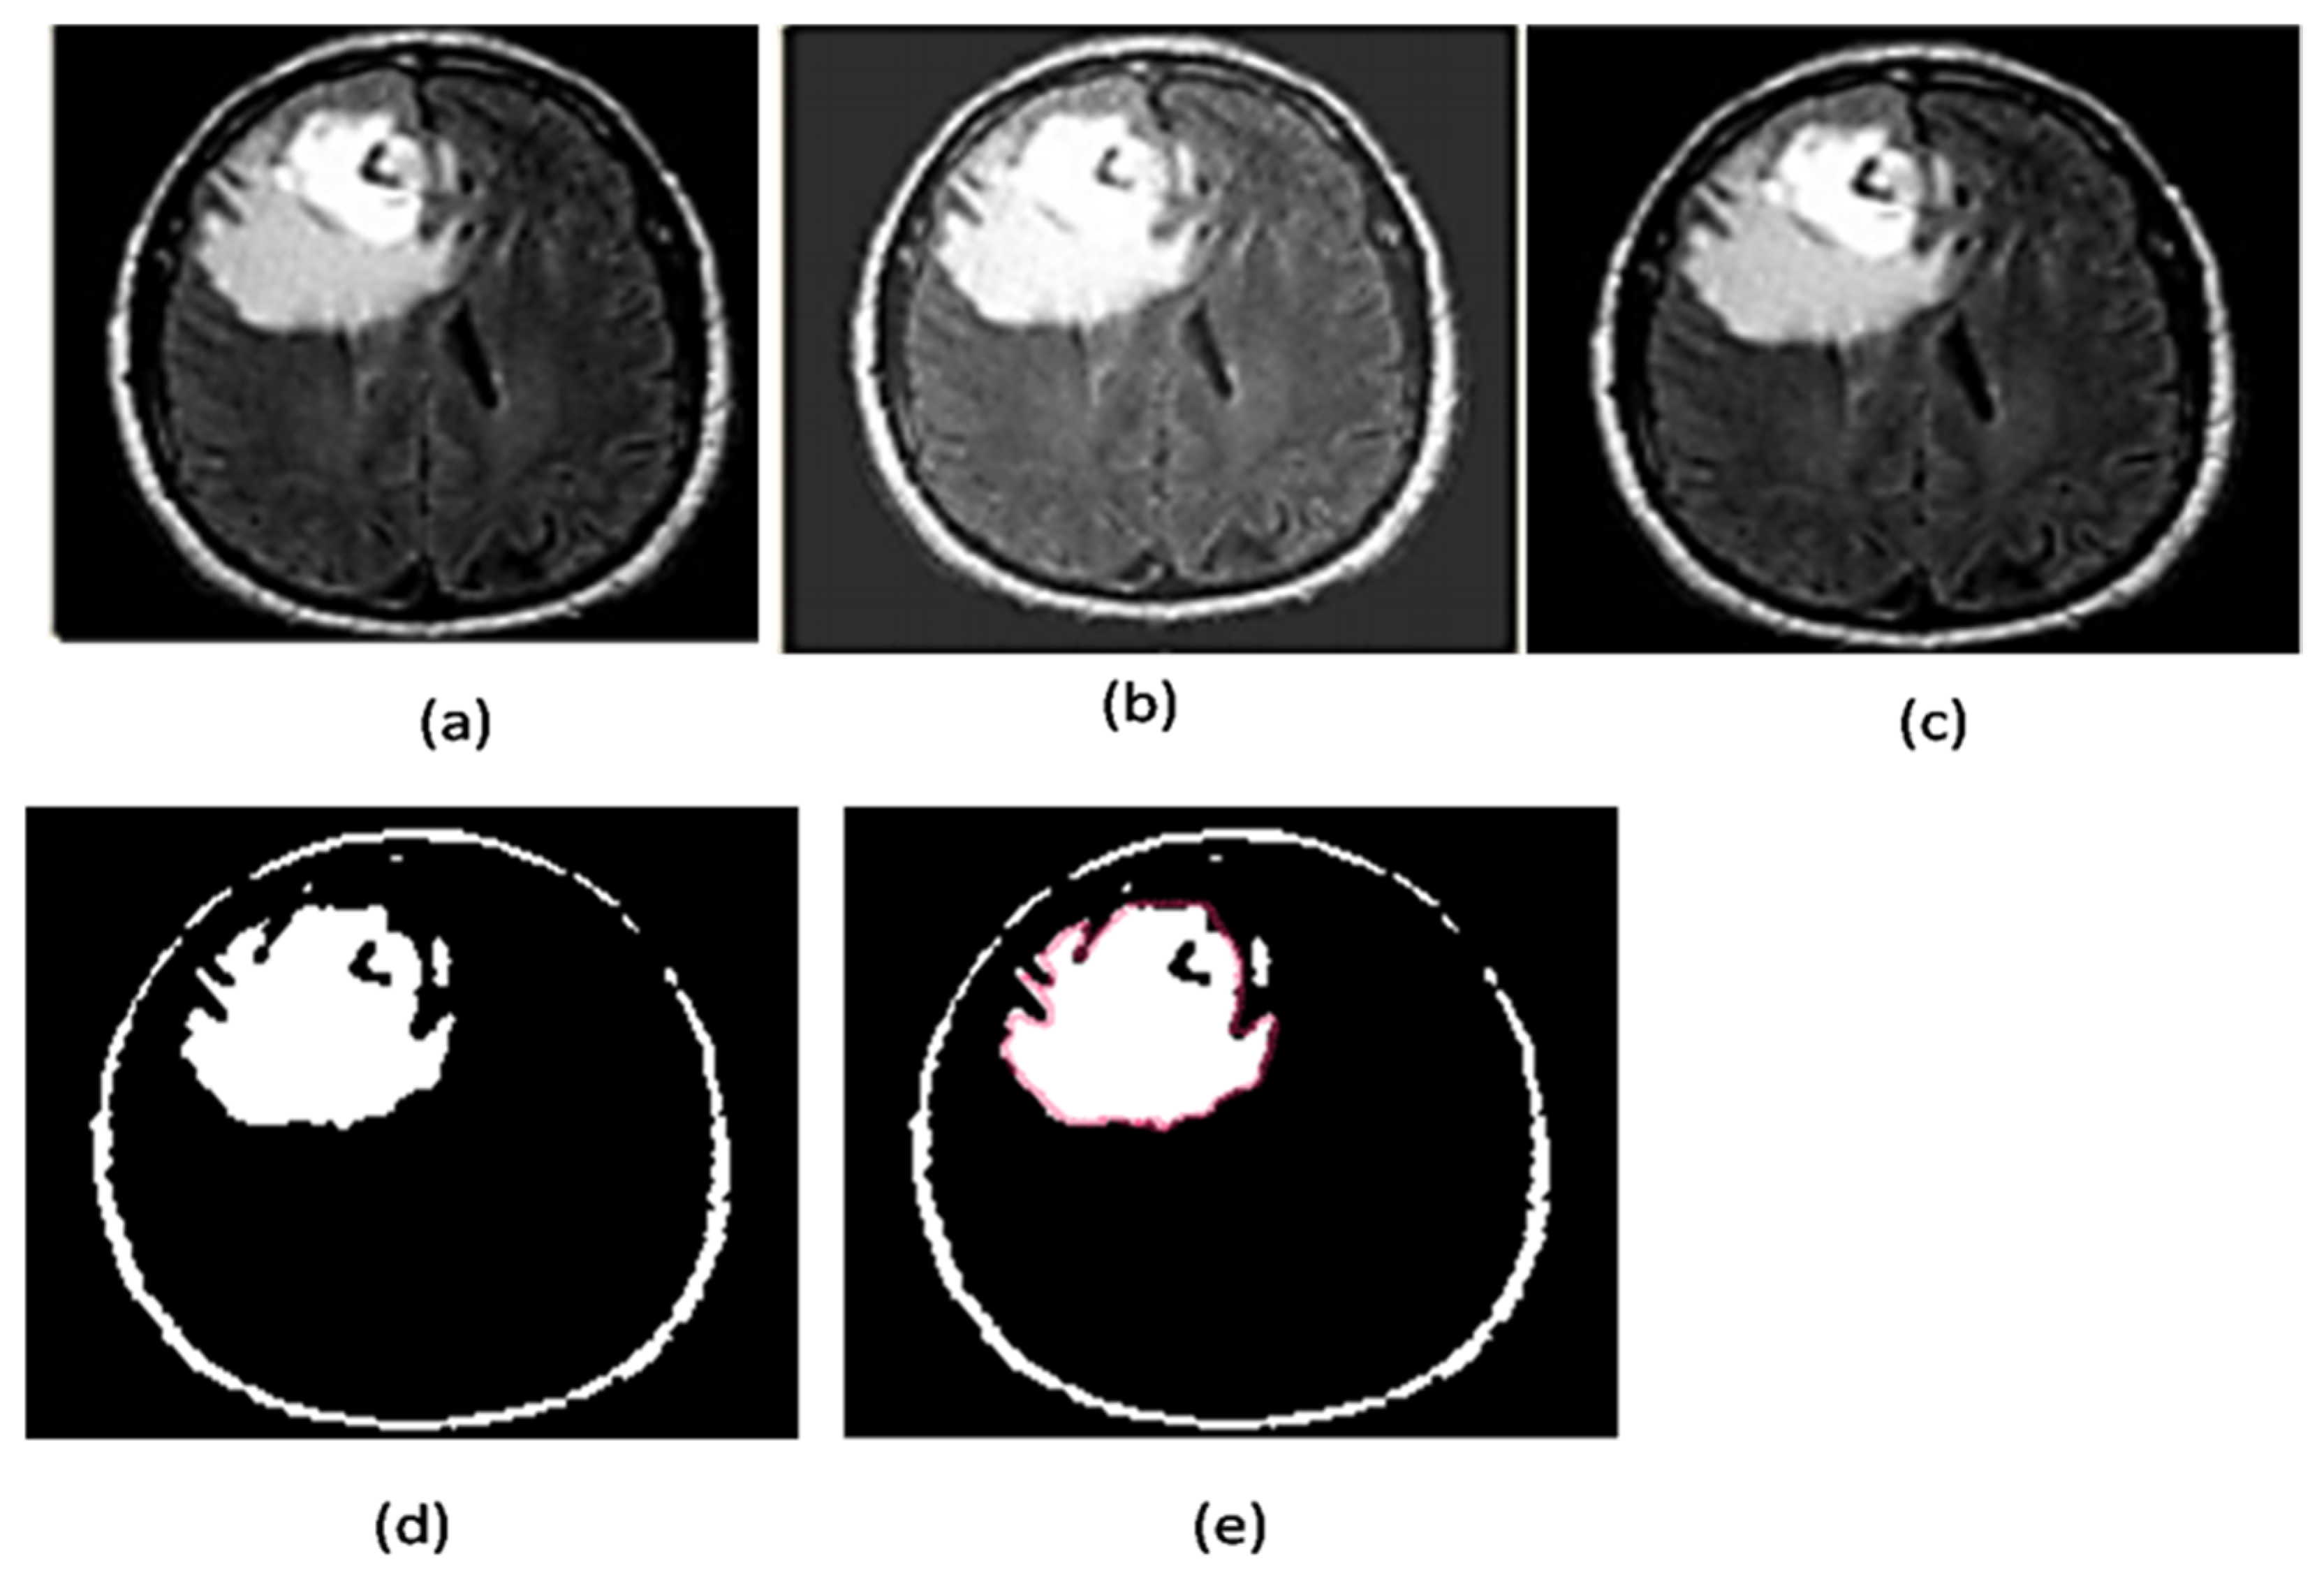

2.2.7. Area Segmentation using Watershed Algorithm

2.2.8. Region Masking and the Separation

2.3. Proposed a Colorized Method for Masked Area Colorization

- Strel: this command is used to create elements of morphological structure;

- Imerode: this function shrunk (eroded) the image;

- Imdilate: this function dilated the image and filled the areas after expanding.